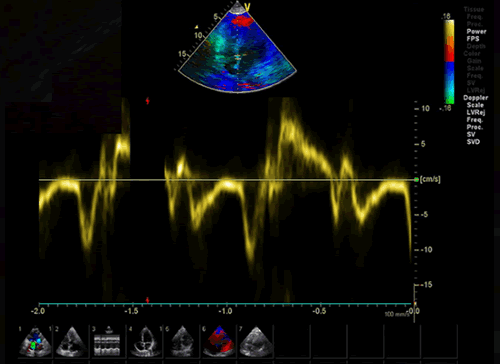

3.ドプラ計測の実際

2.ドプラ計測時のポイントと注意点